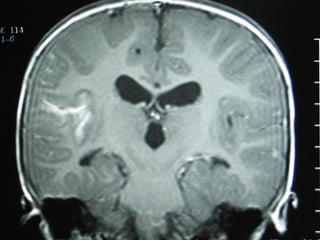

Meningitis tuberculosa

– Diseminación hematógena: con frecuencia

TB miliar asociada

– Mayoría menores de 3 años

– LCR: Leve pleocitosis de predominio

mononuclear, hipoglucorraquia e

hiperproteinorraquia

– Mantoux e IGRA: Con frecuencia negativo

– Síntomas inespecíficos: Alto grado de

sospecha clínica